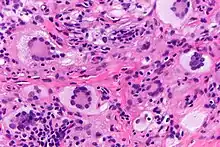

Histiocytic disorders like JXG are identified by the cells that make them up.[4] Immunohistochemical analysis is used to discern the immunoreactivity to certain antibodies in these analyses. JXG is a non-LHC disorder which is a varied group of disorders defined by the accumulation of histiocytes that do not meet criteria to be diagnosed as Langerhans cells. JXG is not metastatic and may be present with lipid deposits. JXG is often accompanied with other disorders such as neurofibromatosis type one and juvenile chronic myelogenous leukemia. Juvenile variety xanthogranuloma can be distinguished from xanthoma by the spread of the lesion and the lack of lipid abnormalities. Other similar diagnoses include molluscum contagiosum, hemangioma and neurofibroma.[4]